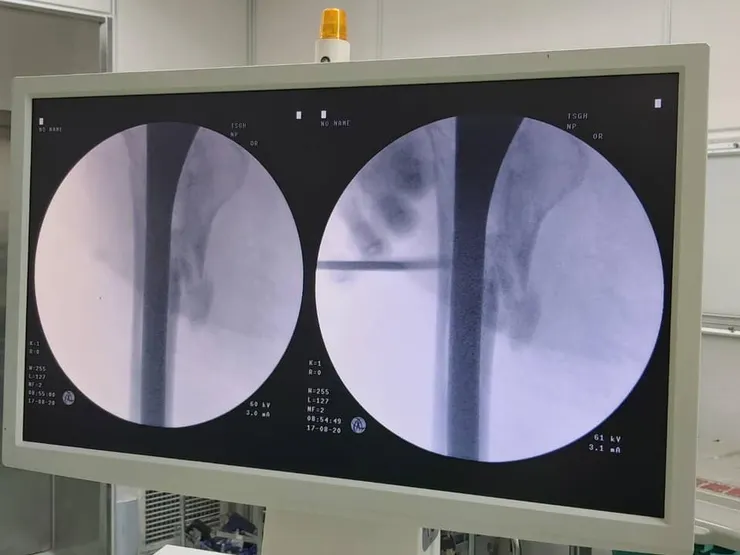

楊健福表示,大多數人認為膝關節退行性變是只在老年時才會出現的問題,但事實並非如此。楊健福進一步表示,軟骨的磨損不僅會導致膝關節退化,長期還會對韌帶和肌肉造成損傷,導致膝關節發炎,造成不可逆的損傷。大多數患者是中年人——年齡在 4 到 50 歲之間,這證明了預防性治療和早期干預關節的重要性。此外,傳統的人工關節置換術常用於治療骨關節炎,可以有效解決膝關節退變問題,但也有其局限性, 楊健福指出,人工關節畢竟是異物,存在感染風險。

楊健福介紹,這種再生醫學治療在烏克蘭需要2-300萬台幣,費時又費力,由於俄羅斯與烏克蘭的戰爭關係以及不穩定的國際局勢,實際上是台灣的機會。楊健福和戴念國目前正在研究的再生醫學療法,使用自體脂肪提取,只需3-4小時培養細胞,節省大量時間和金錢。楊健福說,再生醫學將為未來的臨床提供機會,通過縮短治療時間,使人們的生活更加便利並重獲尊嚴。